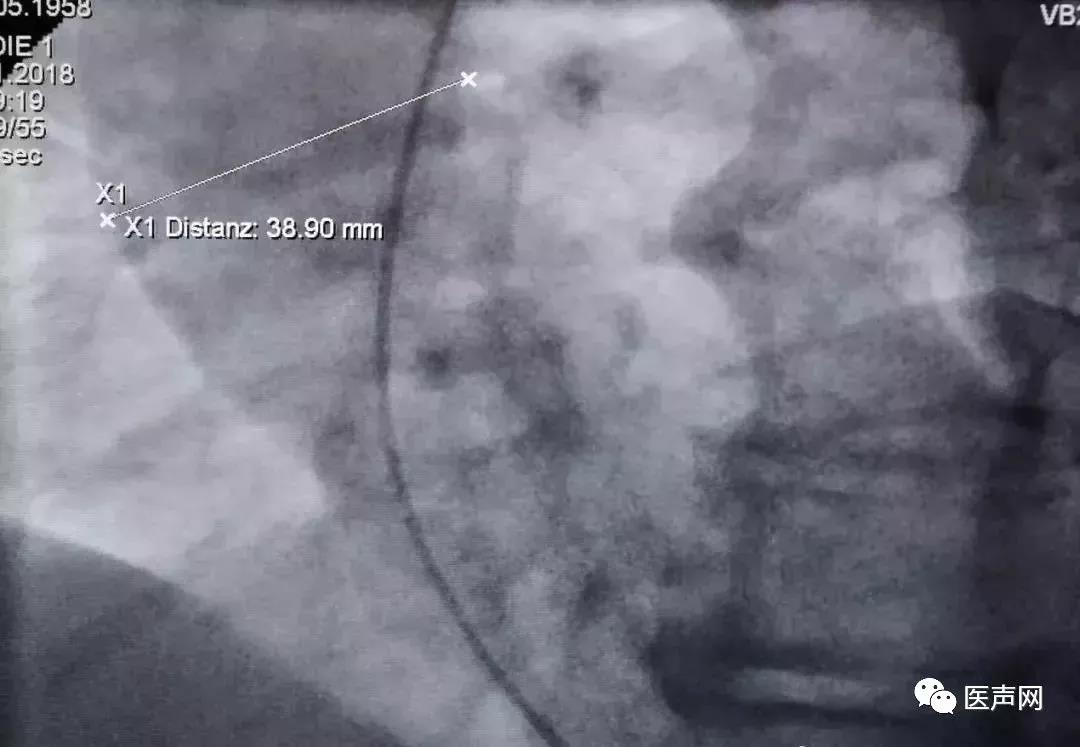

通过左心室造影除了可以检测主动脉瓣跨瓣压差外(该患者压差为49mmHg),还可以测量主动脉根部的宽度(图6),了解主动脉根部有无增宽或者瘤样扩张,主动脉管壁有无钙化及是否扭曲等。如果肾功能没有明显障碍,尽可能进行左前斜及右前斜两个体位的造影。

图6:左心室造影后,取静态图,选择主动脉根部最宽部位测量其直径,该患者最宽为38.9mm,提示没有主动脉增宽及瘤样扩张。